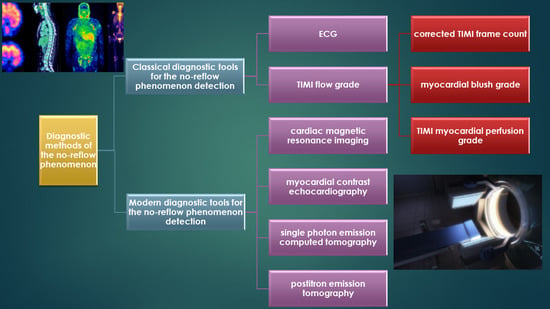

5. Diagnostic Methods of the No-Reflow Phenomenon

5.1. Classical Diagnostic Tools for the No-Reflow Phenomenon Detection

5.1.1. ECG

5.1.2. Coronary Angiography

TIMI Flow Grade

CTFC

MBG

TMPG

5.2. Modern Diagnostic Tools for No-Reflow Phenomenon Detection

5.2.1. CMRI

5.2.2. MCE

5.2.3. SPECT

5.2.4. PET

5.3. Classical Versus Modern Diagnostics Methods of the No-Reflow Phenomenon